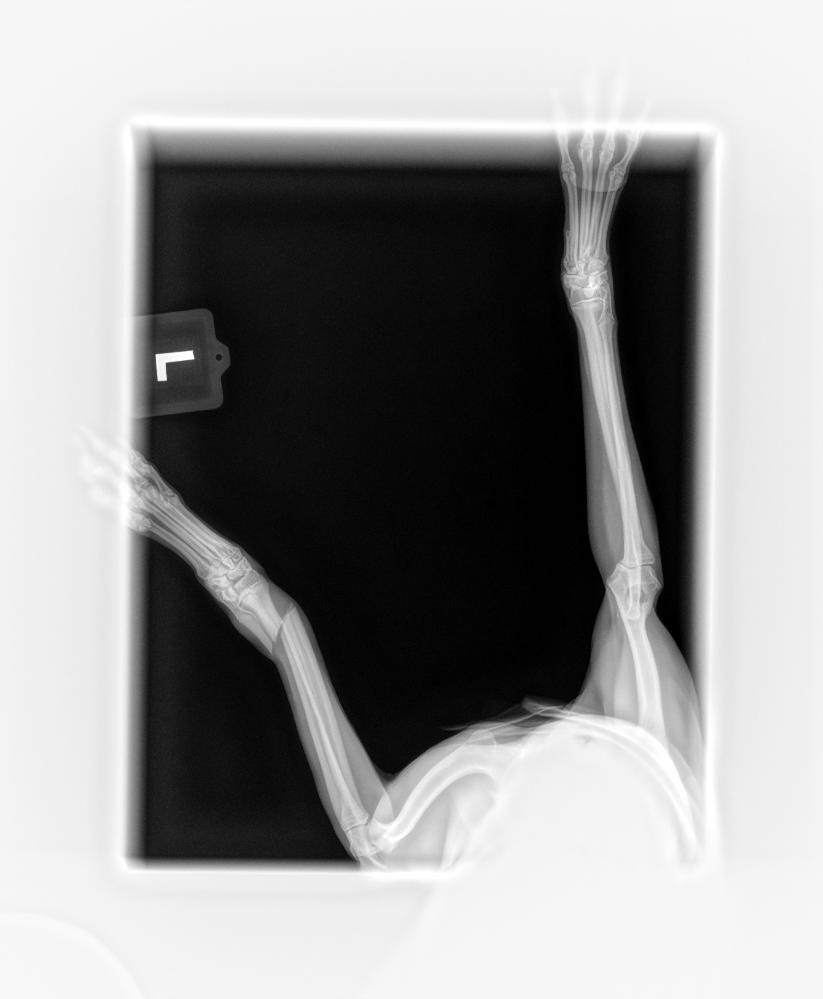

My name is Carrie Schmidt and on June 28th, 2025, my Italian Greyhound, Kala, broke her leg. We cannot afford the surgery she needs to put a plate in. She cannot be left alone all day, so my daughter volunteered to quit her job and stay home to care for Kala, which brings us down an income. We have been trying the splinting it every week at $95 a week for 8-10 weeks, but after an X-ray yesterday, it has been confirmed that she will need surgery due to both bones in her arm being broken and the splint not helping with any twisting motion she does. She is an 8-month-old puppy full of energy, so this is very hard on all of us. When I get the estimate from the vet, I will post it here and adjust the goal accordingly. If we cannot meet our goal and get her the surgery, then she is most likely going to need an amputation. I really don't want to have to amputate since that will leave her at a very high risk of breaking the other front leg. Please, if you can donate anything at all, it would be greatly appreciated! You can also donate directly to the vet under our names: Ciara Roberts/Kala Wilson's veterinary hospital, [phone redacted]